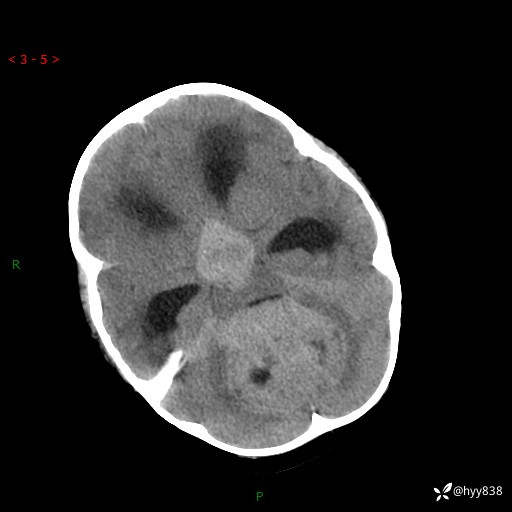

性别:女

年龄:3岁

简要病史:发现行走不稳2个月,加重1个月

颅脑CT平扫

三脑室、四脑室多发病变,如何分析?

髓母细胞瘤 (13)